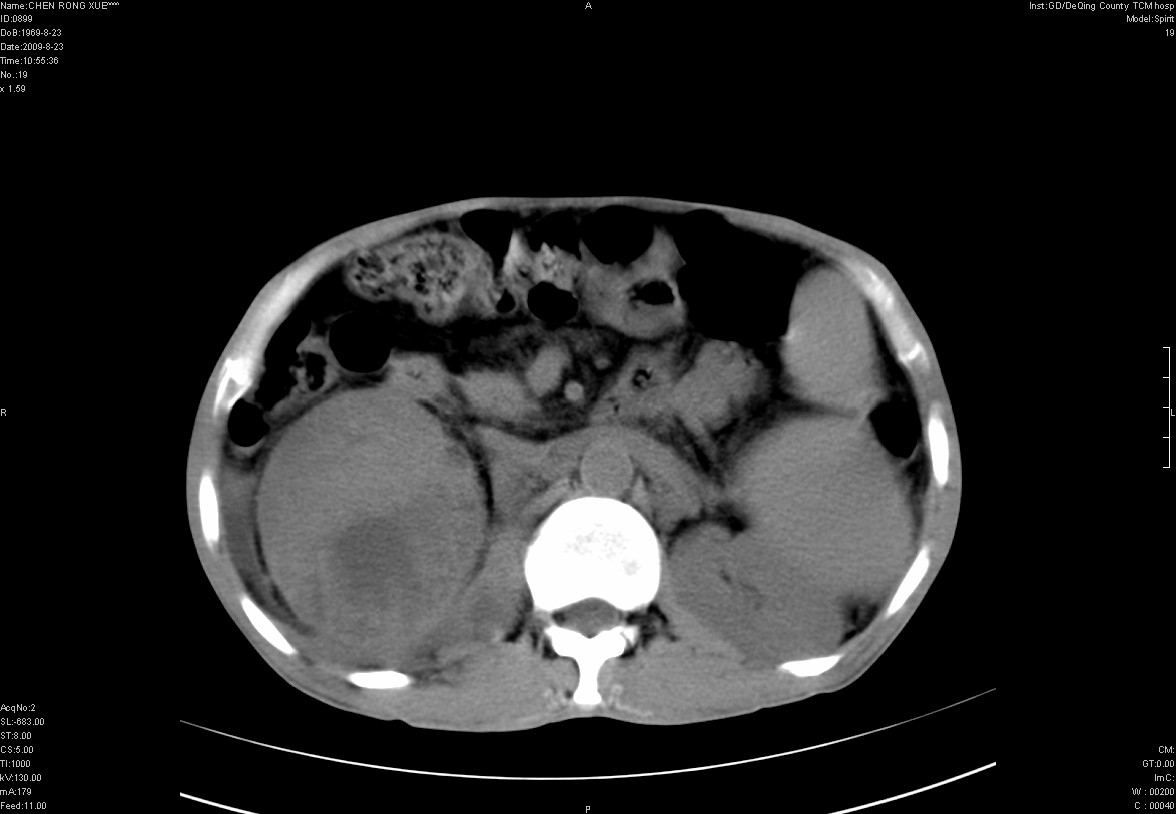

以下是引用zxl51642在2009-8-23 12:56:00的发言:[br]1、肝硬化、脾大;2、慢性胆囊炎;3、右肾占位并右侧腰大肌受侵,考虑恶性可能性大,建议增强扫描进一步检查。

以下是引用qiuleiyu在2009-8-23 15:17:00的发言:[br]1、慢性肝病,肝硬化,脾大,门脉高压。胆囊小结石。[br]2、右肾明显肿大,伴片状低密度灶,累及右侧腰大肌,肿瘤及炎症性病变皆有可能大,建议增强。

以下是引用zjzjr在2009-8-23 17:42:00的发言:[br]1、慢性肝病,肝硬化,脾大,门脉高压。胆囊小结石。[br]右肾脓肿波及肾周,建议增强

以下是引用dyqct在2009-8-23 16:53:00的发言:[br][quote]以下是引用qiuleiyu在2009-8-23 15:17:00的发言:[br]1、慢性肝病,肝硬化,脾大,门脉高压。胆囊小结石。[br]2、右肾明显肿大,伴片状低密度灶,累及右侧腰大肌,炎症性病变可能,建议增强。